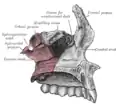

Interior da superfície lateral.

Interior da superfície lateral. -